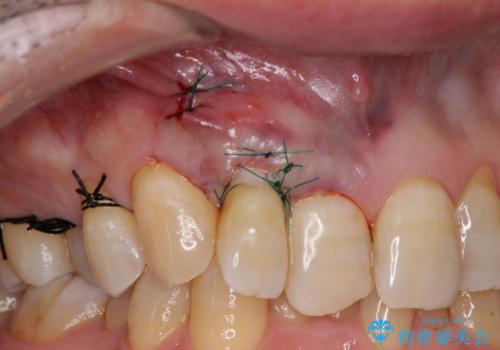

口蓋(上顎の内側)から採取した結合組織(歯肉の内側の組織)を移植することによる、根面被覆術を行うこととしました。

ディープバイトで咬合力が強く、該当歯に負担のかかりやすい咬み合わせであったため、歯肉退縮が起こりやすいと判断された患者様でした。

根面被覆を達成するとともに、歯肉の厚みを増すことで、今後歯肉退縮を起こしにくくするよう配慮した処置としました。